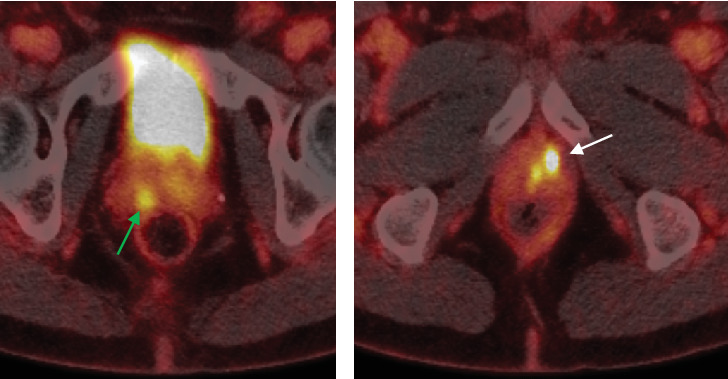

Patient selection for focal therapy (FT) of prostate cancer requires the assessment of MRI and biopsy results. However, there is currently little guidance for the utility of PSMA PET/CT in FT planning. We describe the case of a man originally considered an ideal candidate for FT based on biopsy and MRI who was found to have a contralateral lesion-harboring cancer detected only on PSMA PET/CT. Trial Registration: ClinicalTrials.gov identifier: NCT05852041.